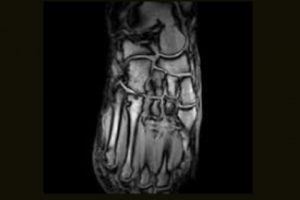

When you need high-quality extremity MRI, the O-scan dedicated MRI system is the perfect fit. The O-scan system’s complete range of extremity imaging capabilities, intuitive operation, and compact footprint combine to provide the optimal solution for both patients and practices.